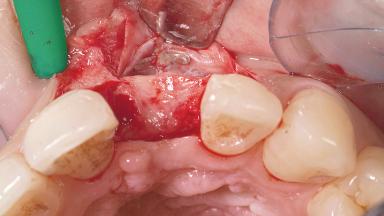

A 30-year-old female patient had lost tooth 21 and was referred to our clinic for consultation and treatment. Due to advanced apical infection, tooth 21 had been extracted two months earlier at another clinic and an acrylic-resin tooth had been bonded to the adjacent teeth. The patient desired implant treatment to avoid any damage to the adjacent natural teeth. While the patient had no history of any systemic disorder, she was a heavy smoker and exhibited medium to advanced periodontitis in the entire jaw. After the initial treatment to achieve a pocket probing depth of less than 4 mm and no bleeding on probing, a decrease in the height of the papillae mesial and distal to the extraction site and overall gingival recession were observed.

Bone Augmentation Horizontal|Staged

Augmentation Materials Autogenous chips|Membrane

Soft Tissue Grafting Simultaneous

Soft Tissue Anatomy Intact Defective